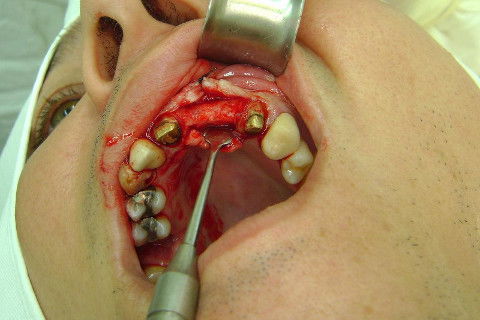

Cirurgia realizada hoje de manhã...No planejamento percebi medindo espessura do rebordo com especímetro que as medidas não estavam muito boas, ou o ideal, em torno de 4,5 a 5 mm ate´o terço médio do rebordo e melhorava no final, com 6 a 7 mm. Optei então por uma pequena expansão usando os expansores rosqueáveis. Aconteceu uma pequena fenestração na hora da fixação dos implantes, especialmente na região do 22 que fraturou o início da tábua óssea, mas não me preocupei porque não foi mais do que 2 mm de fratura em direção apical, o implante ficou infraósseo e com boa estabilidade (60 N no 21 e 40 N no 22). Esta fratura tb não deixou osso completamente solto, foi do tipo galho verde, deixei em posição e suturei normalmente. Só não fiz e nem estava planejado carga imediata mesmo, mais pelo motivo da oclusão inadequada do caso.

Fotos do caso